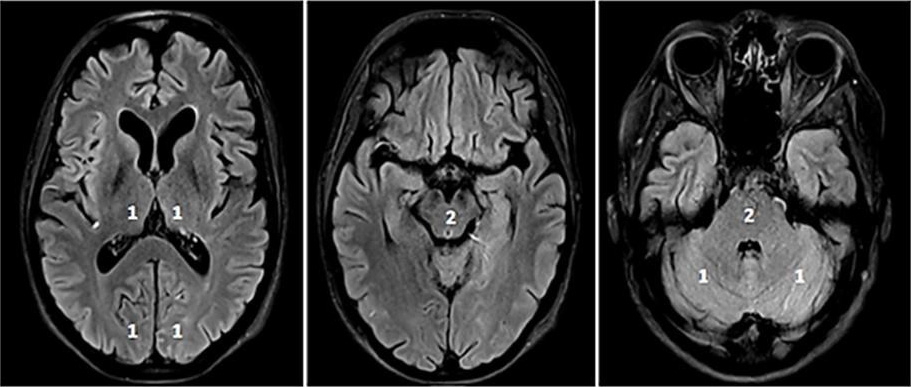

Fig. 2.CT-Perfusion. NCCT ASPECTS 10 (A). CT-A with M2-occlusion (B).

Interpretation of CT-P: the cerebral blood volume (CBV) is symmetrical without a

regional decrease (C). Cerebral blood flow (CBF) is reduced in the posterior MCA

territory on the left (D). The mean transit time (MTT) of the contrast agent (E)

and Tmax (time to maximum; time delay between the contrast agent arrival in the

proximal large vessel arterial circulation and the brain parenchyma perfusion

[F]) are prolonged. The infarct core in CT-P shows a markedly reduced CBF (

pc-ASPECTS

Fig. 3.pc-ASPECTS (posterior circulation ASPECTS). The pc-ASPECTS is a 10-point score evaluating the extent of ischemia in the posterior circulation. Scores of 10 points indicate no signs of ischemia in NCCT or MRI (diffusion weighted imaging, DWI). Each thalamus, occipital lobe and cerebellar hemisphere accounts for 1 point, and the mesencephalon and pons account for 2 points. Fig. 3 shows fluid attenuated inversion recovery (FLAIR) sequences because of better image quality.